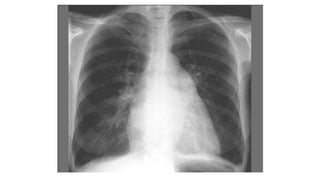

71 Year-Old From

Ghana With Chest

Pain.

Thoracic Artery Aneurysm With Type A Dissection